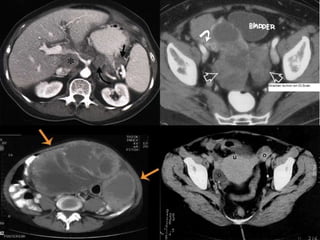

Өндгөвчний хавдрыг илрүүлэх

• Хэт авиан болон компьютер томографын (CT) оношлогоо нь өндгөвчний эдийн бүтэц

өөрчлөгдсөнийг тодорхойлдог боловч өөрчлөгдсөн эд нь хавдар мөн эсэхийг нарийн

тодорхойлж чаддаггүй.

• Иймээс хорт хавдрын өөрчлөлтийн магадлалтай тохиолдол болгонд сэжигтэй эдийг мэс

ажилбараар авч, сорьцыг лабораторийн шинжилгээнд оруулна. Биопсийг зүүний

хатгалтаар эсвэл дурангийн аргаар авч болно

Өндгөвчний хавдрыг илрүүлэх •Хэт авиан болон компьютер томографын (CT) оношлогоо нь өндгөвчний эдийн бүтэц өөрчлөгдсөнийг тодорхойлдог боловч өөрчлөгдсөн эд нь хавдар мөн эсэхийг нарийн тодорхойлж чаддаггүй. • Иймээс хорт хавдрын өөрчлөлтийн магадлалтай тохиолдол болгонд сэжигтэй эдийг мэс ажилбараар авч, сорьцыг лабораторийн шинжилгээнд оруулна. Биопсийг зүүний хатгалтаар эсвэл дурангийн аргаар авч болно